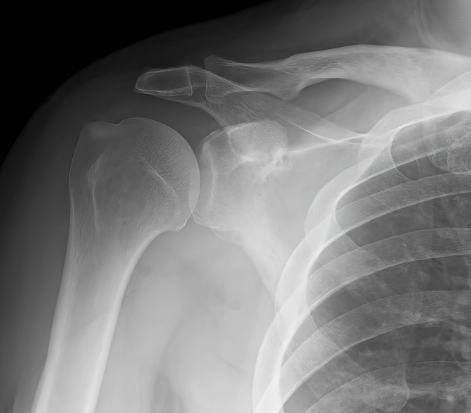

次にレントゲンで肩の石灰化や変形がないかを確認します。

そして、肩の変形がないか石灰化がないかをチェックします。

腱板断裂を疑う方にはエコーやMRI(下の画像)で腱板断裂の有無を確認し、確定診断いたします。